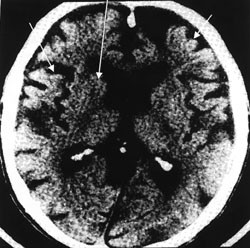

Ved klinisk mistanke om Alzheimers sykdom vektlegges bildemessige tegn på substanssvinn kortikalt, subkortikalt, temporalt og sentralt. Det er flere usikkerhetsmomenter knyttet til vurderingen av substanssvinn på CT (4). For det første fører normal aldring til tap av hjernevev. En viss hjerneatrofi er således fysiologisk i høy alder. Videre er reliabiliteten for grad av substanssvinn ved cerebral CT variabel (5, 6), og gode interobservatørstudier av reliabilitet hvor eldre er inkludert etterlyses. Ved vurderingen av eventuelt substanssvinn ved cerebral CT vil det ofte være usikkerhet om hva som er normalt for alderen. Spesielt i tidlige stadier av Alzheimers sykdom er det tvilsomt om cerebral CT har tilstrekkelig sensitivitet til å være et brukbart diagnostisk hjelpemiddel i vurderingen av temporallappsatrofi, og andelen med falskt positivt funn kan være høy på grunn av vansker med å skille patologiske forhold fra normale aldersforandringer (4) (fig 1). Ved mistanke om Alzheimers sykdom er dette spesielt relevant, da det her foreligger patologisk substanssvinn i hippocampus og perihippokampale deler av hjernebarken tidlig i sykdomsprosessen (7).